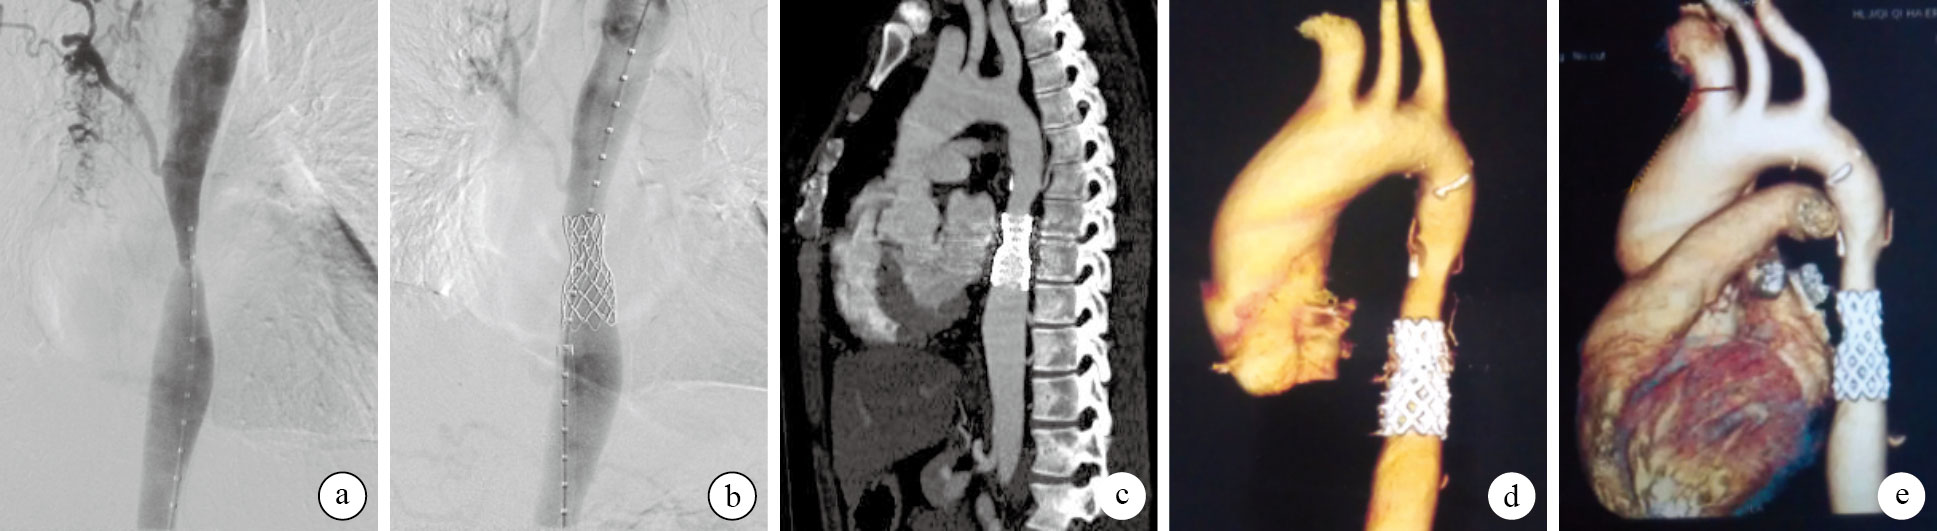

15例患者均順利完成手術。跨縮窄段收縮壓壓差由術前(58.1 ± 19.5)mm Hg下降為術后即刻(6.2 ± 5.6) mm Hg,病變部位狹窄程度由術前73.8% ± 12.8%下降為術后即刻16.7% ± 5.6%,比較差異均有統計學意義(t=12.483,P=0.000;t=15.631,P=0.000)。1例因血管封堵器未能封閉穿刺點,中轉血管縫合后,穿刺點閉合良好,足背及脛后動脈搏動正常;其余患者均成功應用封堵器封閉穿刺點,所有穿刺點愈合良好,無穿刺點動脈夾層、假性動脈瘤及明顯皮下血腫發生,患者術后48 h內均可下床適度行走。本組患者住院時間為6~18 d,平均11.1 d。15例均獲隨訪,隨訪時間1~81個月,平均29.7個月。患者頭暈癥狀均明顯減輕,運動耐量明顯改善;上下肢動脈收縮壓壓差均< 20 mm Hg;末次隨訪收縮壓及舒張壓[分別為(125.2 ± 9.1) mm Hg和(78.5 ± 7.3)mm Hg]均較術前[(162.9 ± 19.6)mm Hg和(91.6 ± 15.3)mm Hg]明顯改善,差異有統計學意義(t=7.725,P=0.000;t=3.651,P=0.000)。主動脈造影示支架位置正常,形態良好,無夾層及動脈瘤形成,無再縮窄或再狹窄發生(圖 1)。